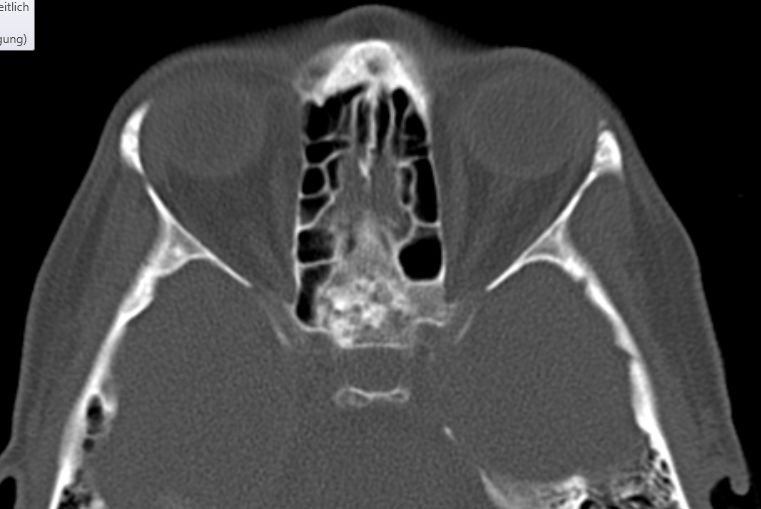

Frontobasis-Tumor

50-jährige Frau (I251), die vor 7 Jahre ein Mammakarzinom (rechts oben außen, T1c No Mo, invasiv NST hatte. Bisher metastasenfrei. Jetzt vor der Sella, in der linken Keilbeinhöhle eine z.T. verkalkte Raumforderung. 2 Jahre unverändert kontrolliert.